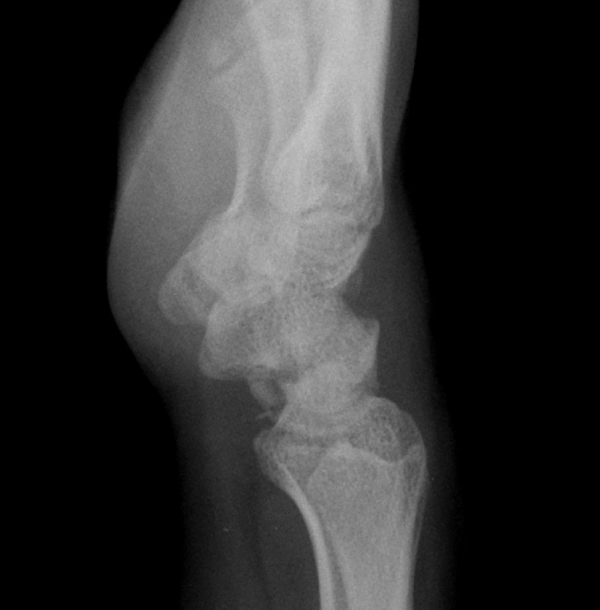

ÃÊÀ½ÆÄ°Ë»ç : ¼Õ¸ñ ¹èÃø Á¾´Ü¸é°Ë»ç¿¡¼­ ¼ö±Ù°üÀý³» ¼ö¾×Àú·ù°¡ °üÂûµÊ(»çÁø 1).